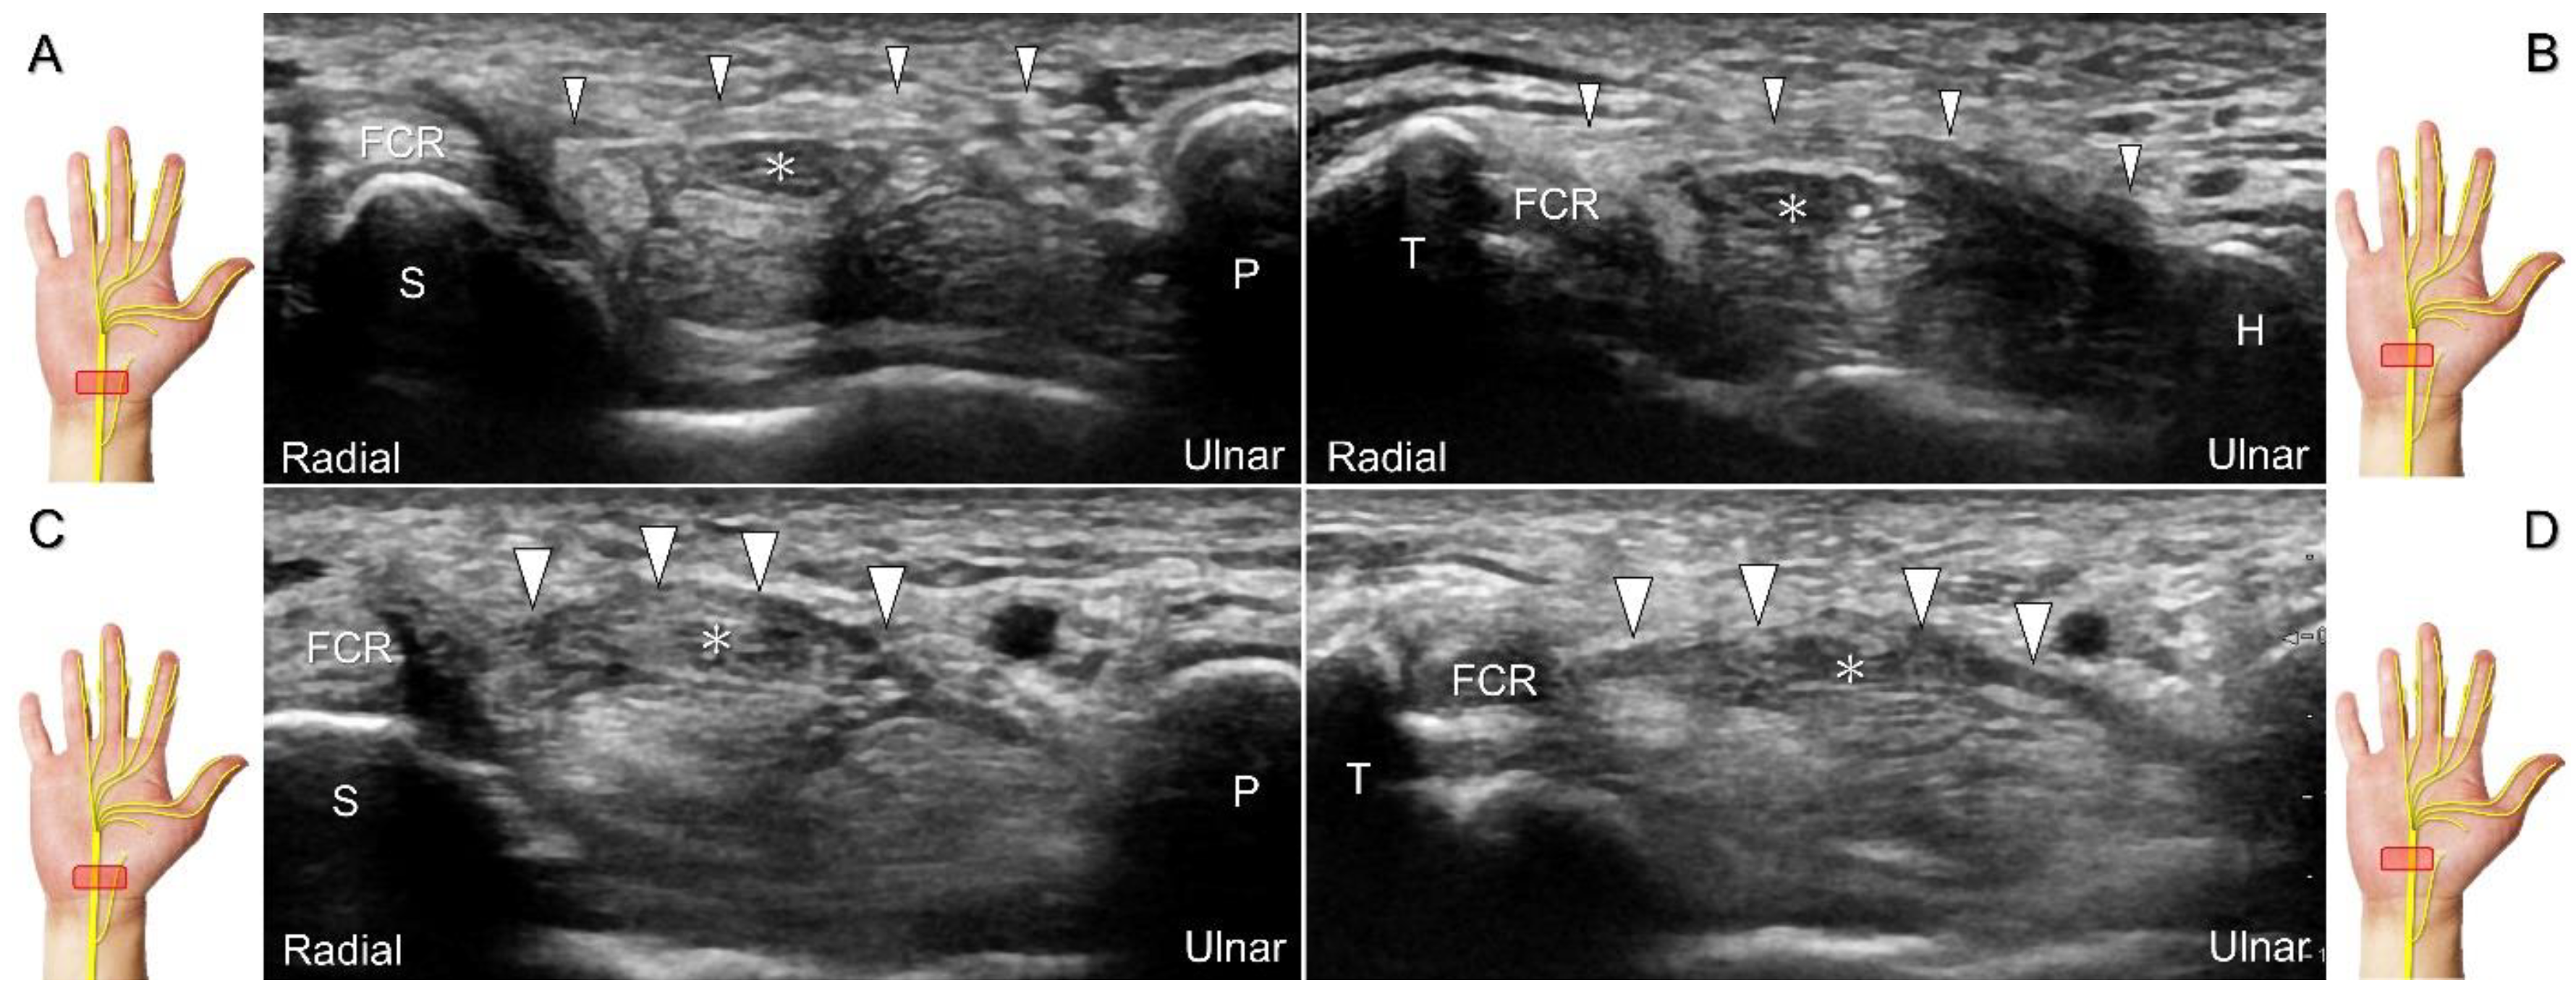

The transducer can be placed in the axial plane on the distal one-third of the forearm with the forearm supinated. The median nerve travels between the flexor digitorum superficialis and flexor digitorum profundus muscles. It gradually runs superficially to enter the carpal tunnel. The carpal tunnel inlet is defined as the plane crossing the scaphoid and pisiform (Figure 2A), whereas the plane linking the trapezium and hook of the hamate serves as the carpal tunnel outlet (Figure 2B).

Clinical Implication

Carpal tunnel syndrome is the most common entrapment neuropathy whereby the median nerve is entrapped by various causes, like hypertrophy of the flexor retinaculum (Figure 2C,D) and compression from the accessory muscles, swollen tendons, ganglions, and bony fractures within the tunnel. Ultrasonographic changes encompass swelling proximal to the entrapment site (Figure 3A), flattening over the entrapment site (Figure 3B), intraneural hypervascularity (Figure 3C), and focal loss of the trimline pattern (Figure 3D).

Figure 2. Sonographic/normal imaging of the median nerve from the inlet (A) to the outlet (B) of the carpal tunnel. Hypertrophy of the flexor retinaculum at both the inlet (C) and outlet (D) of the carpal tunnel. Asterisk: median nerve; small white arrowheads: normal flexor retinaculum; large arrowheads: hypertrophy of the flexor retinaculum. FCR: flexor carpi radialis; S: scaphoid; P: pisiform; T: trapezium; H: hook of the hamate.

Diagnostics 13 01928 g002